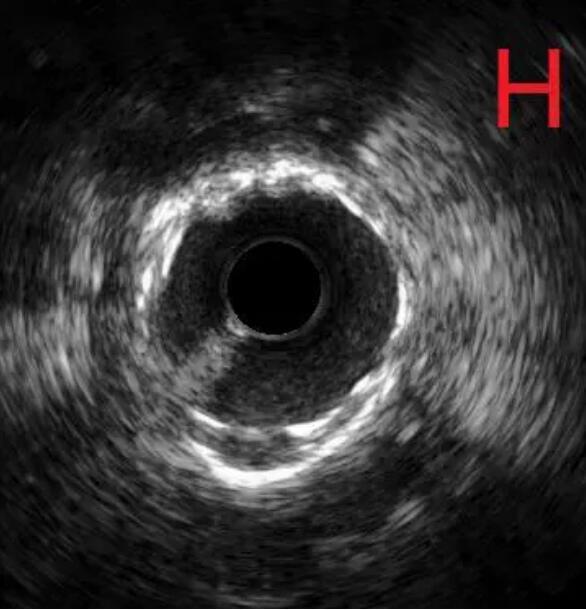

对冠状动脉造影及IVUS图像进行综合判断,目前已经具备安全进行冠状动脉支架治疗的条件,于是在病变处植入支架治疗,随后在IVUS指导下采用后扩球囊改善贴壁情况,顺利完成手术(图G、H)。